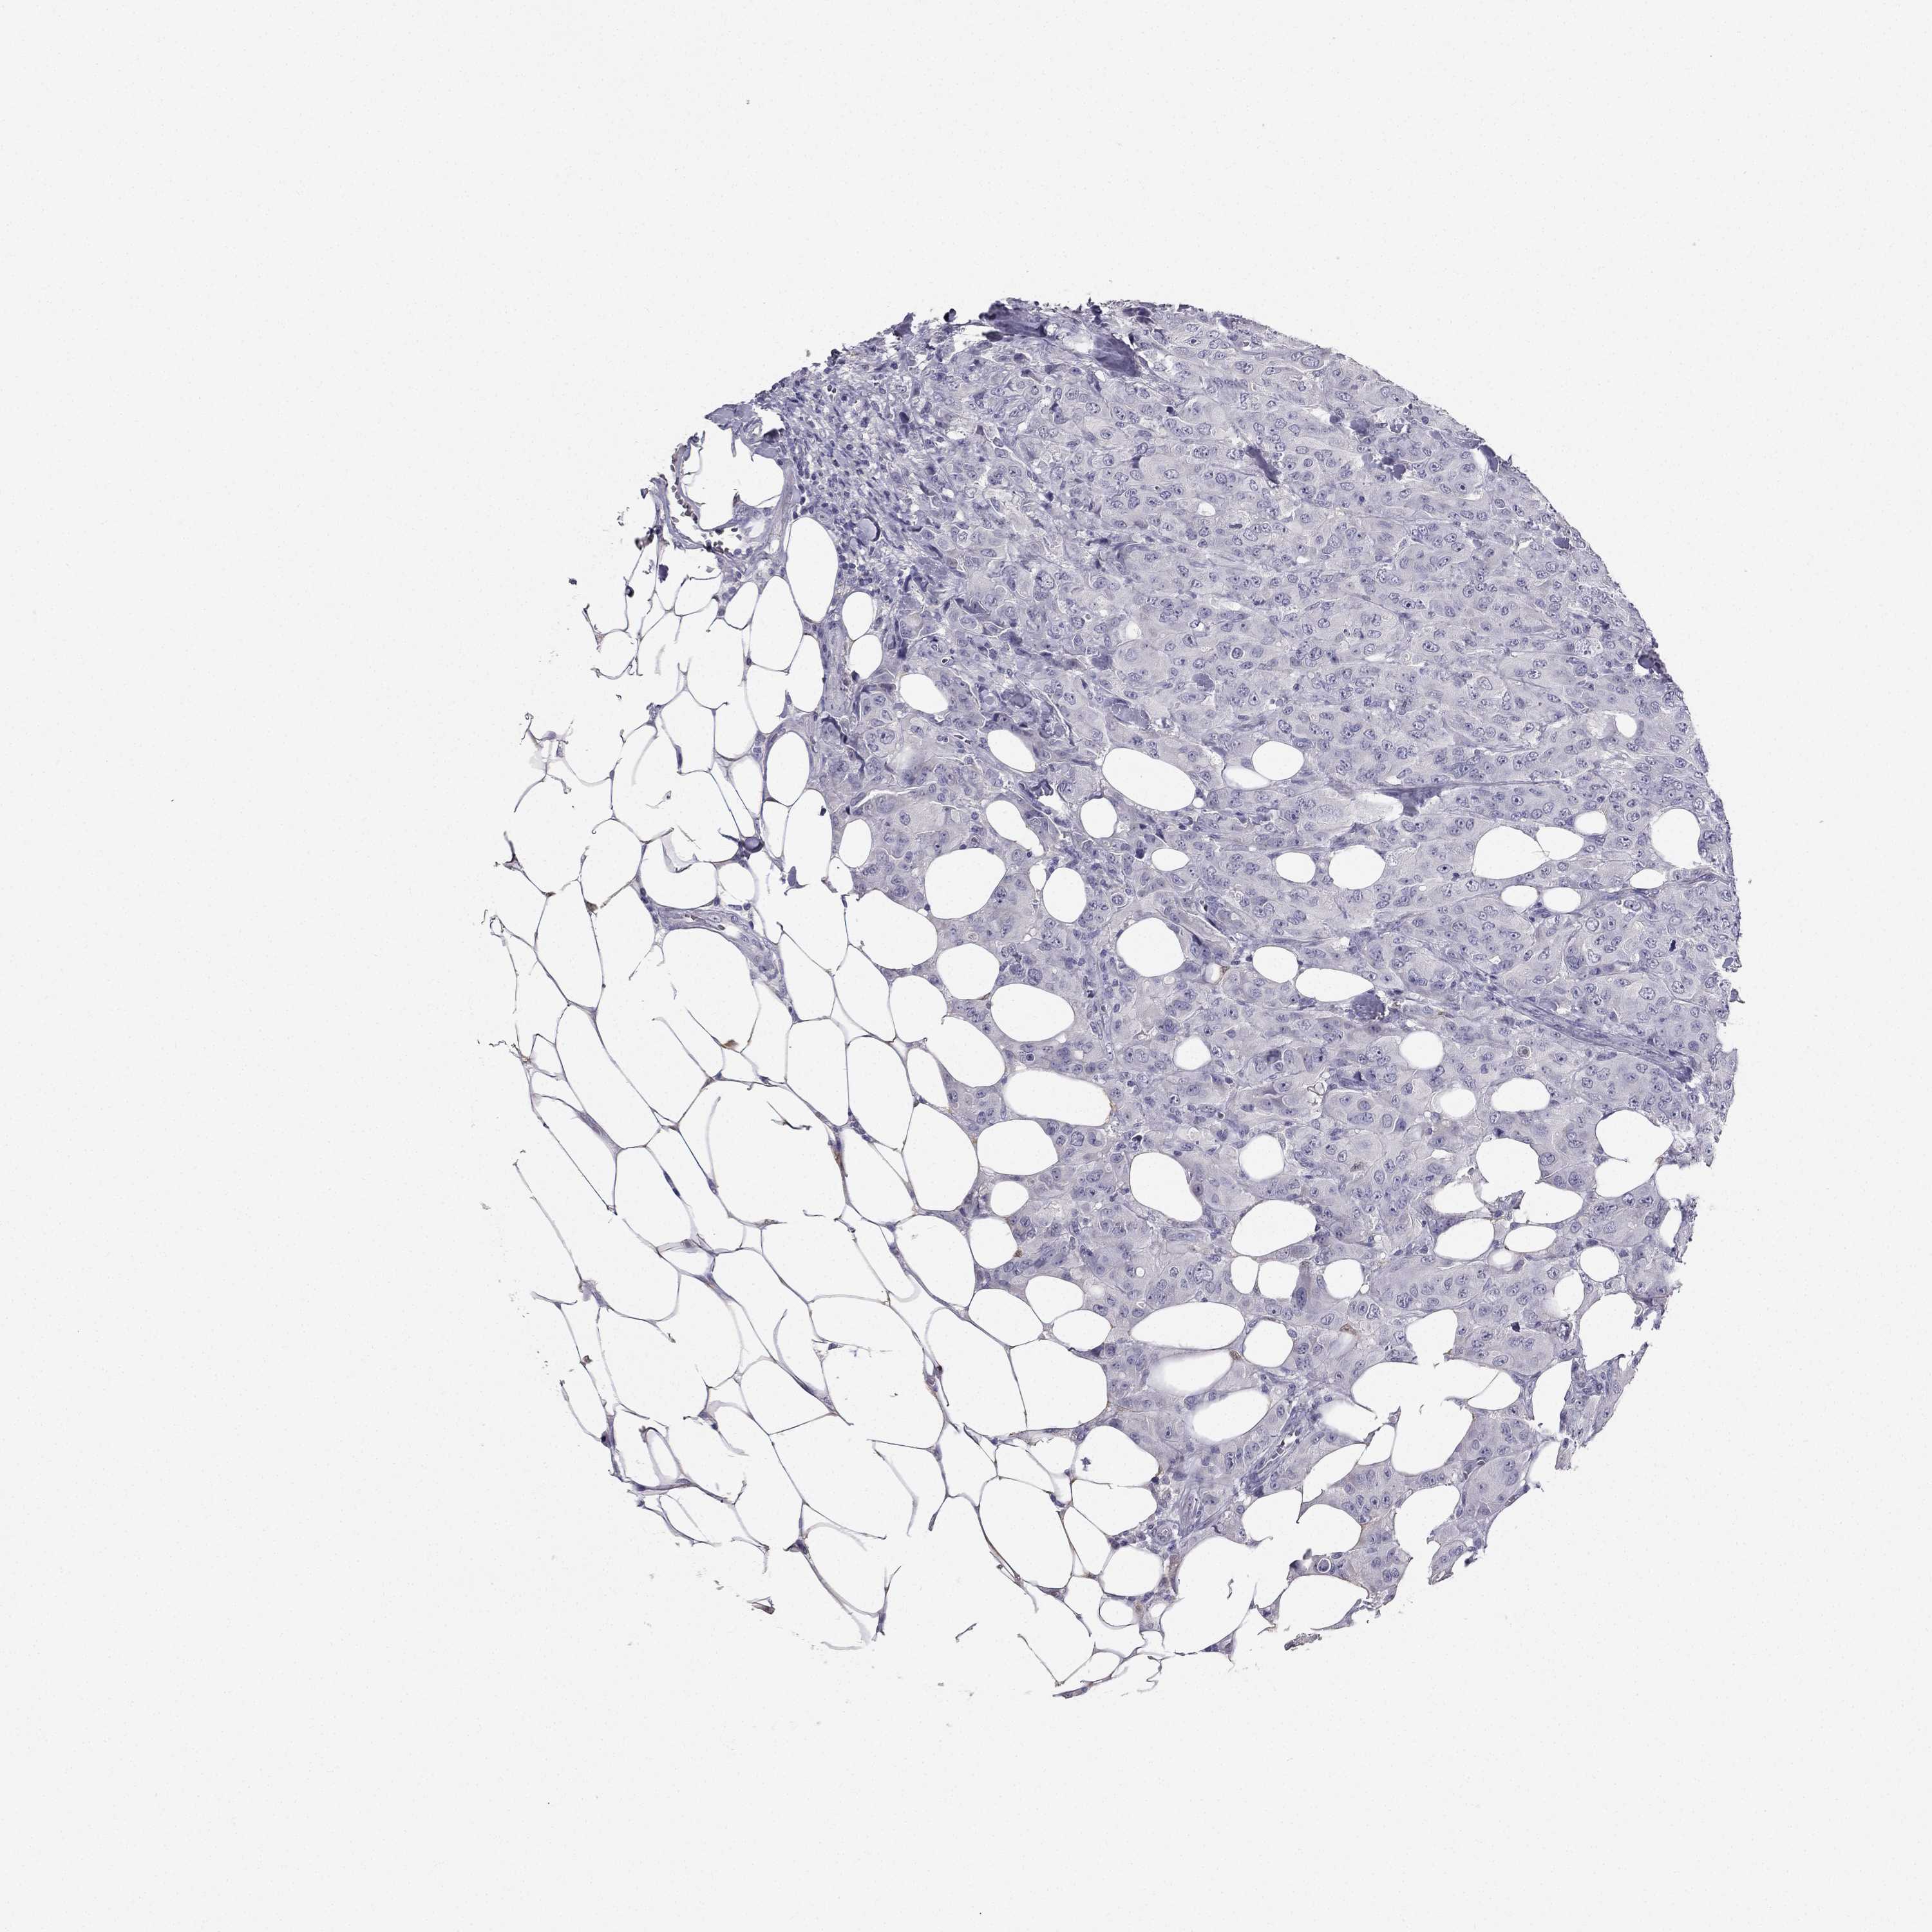

BRCA TCGA BRCA VALIDATION PROTEIN EXPRESSION

Breast cancer

Human cancer